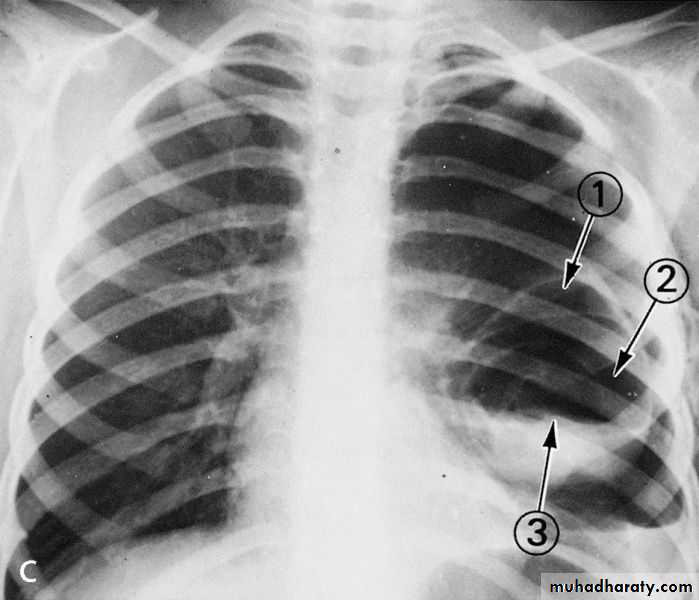

Pneumothorax

A: before treatmentB: after treatment